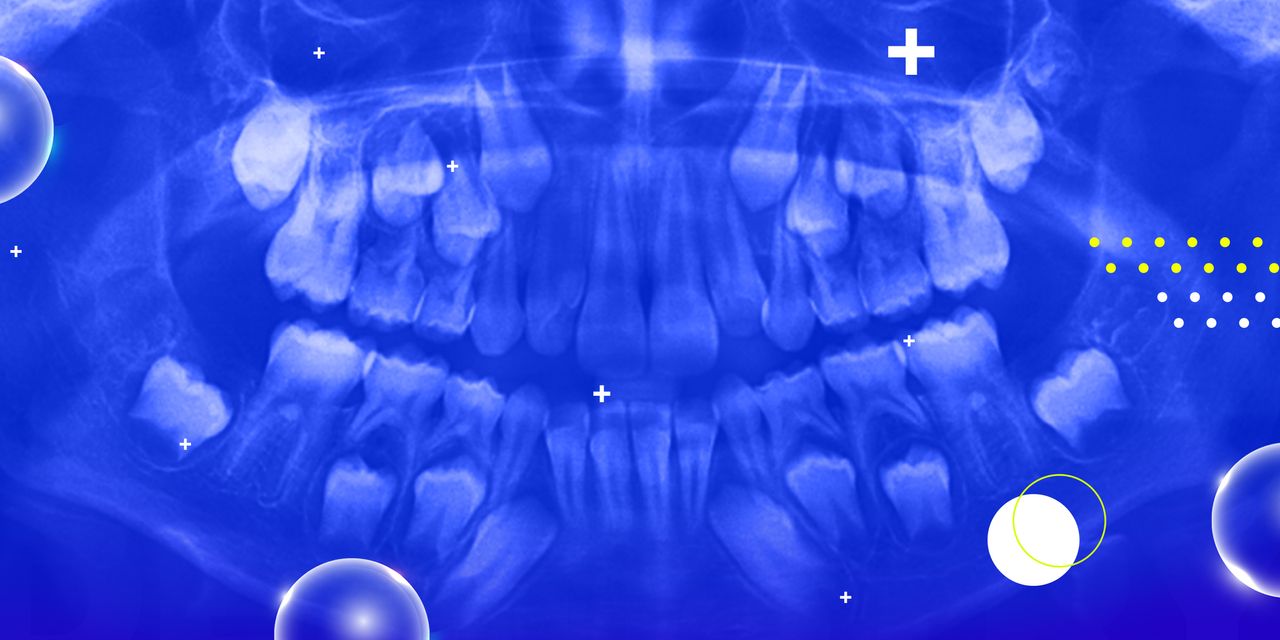

Pediatric Oral Pathology: From Soft Tissue Lesions to Canker Sores

This seminar will provide to the attendee with the most up-to-date information regarding the fascinating and emerging field of oral pathology in pediatric dentistry. The seminar will use case-presentation as the learning and discussion format and will cover the entire spectrum of the most common oral soft tissue lesions in infants, children and adolescents.

– Understand the importance of “building” a differential diagnosis based on the clinical presentation of oral lesions

– Learn the most common soft tissue lesions in infants, children, and adolescents

– Learn the most updated treatment for some of the most common oral conditions besides gingivitis and dental caries.